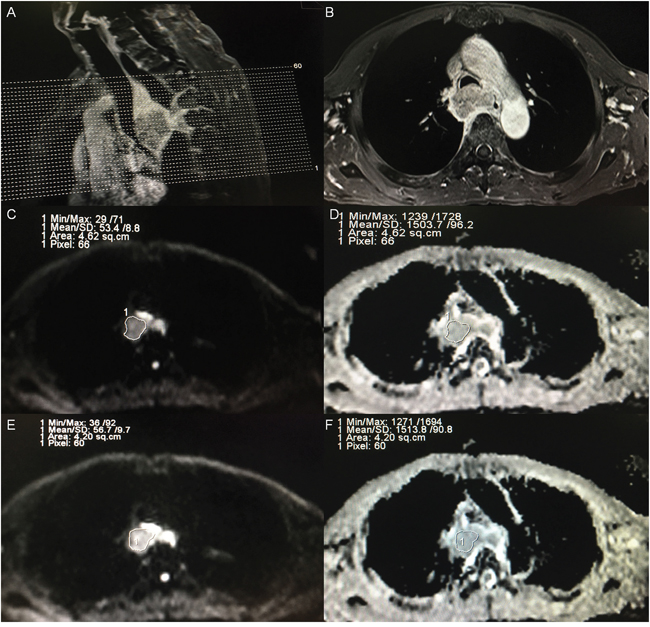

Our study specifically addressed ROI selection strategies to estimate intra- and inter-observer reproducibility. The method of ROI contouring in our study relied on the following strategies: (1) ROI in the slice containing the most enhanced voxels in enhanced contrast T1WI and excluded the necrotic areas to avoid intra-tumoral variation [9, 17, 18], and the point was widely recommended for the measurement of ADC; and (2) Selection of three continuous sections, including the largest slice, to determine the average ADC of the tumor (Figure 5). Our method was derived from previous studies [19, 20] where the delineation was based on the largest slice, but the ROI our study was not confined to the largest slice to assure low variance during the period of ROI delineation. Our data suggest that this is an appropriate strategy to assure the reproducibility of intra-observer and inter-observer. Furthermore, the resulting bias and limits of agreement measurements were acceptable, and low variance in ADC measurements was indicated by the parameter SD. Our results were consistent with Kwee et al. [21] who determined that semi-automated volumetric ADC measurements were more reproducible than manual ADC measurementxoldaxas. However, Kwee et al. [22] revealed that despite good inter- and intra-observer reproducibilities, the ADC value was not always sufficiently reproducible to discriminate malignant from non-malignant lymph nodes.

Figure 5: Example of ADC measurements of a primary tumor in a patient diagnosed as esophageal carcinoma before treatment. (A) A sagittal view with position line of T1-weighted plus contrast-enhanced (T1+C) image for the primary tumor. (B) A transverse view of T1+C image for the one of three continuous sections with maximal diameter of tumor according to the sagittal and transverse view. (C) A region of interest (ROI) was placed manually for observer A in the selected section, on the image obtained at a b-value of 1000 s/mm2, and the ROI was then copied and pasted onto the ADC map (D), and the ADC and SD of the selected section were automatically calculated. (E) A region of interest (ROI) was placed manually for observer B in the selected section, on the image obtained at a b-value of 1000 s/mm2, and the ROI was then copied and pasted onto the ADC map (F), and the ADC and SD were also automatically calculated.